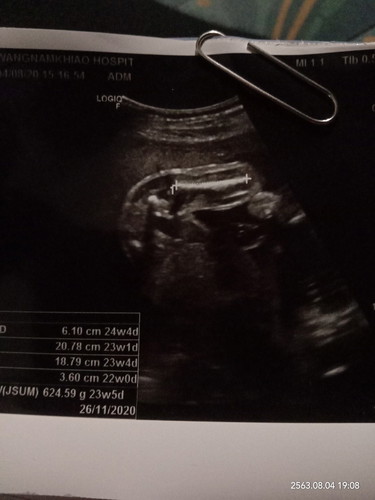

คุณหมอวัดกระดูกต้นขาค่ะ

ส่วนของกระดูกต้นขาจ้า

กระดูกต้นขา Femur ค่ะ